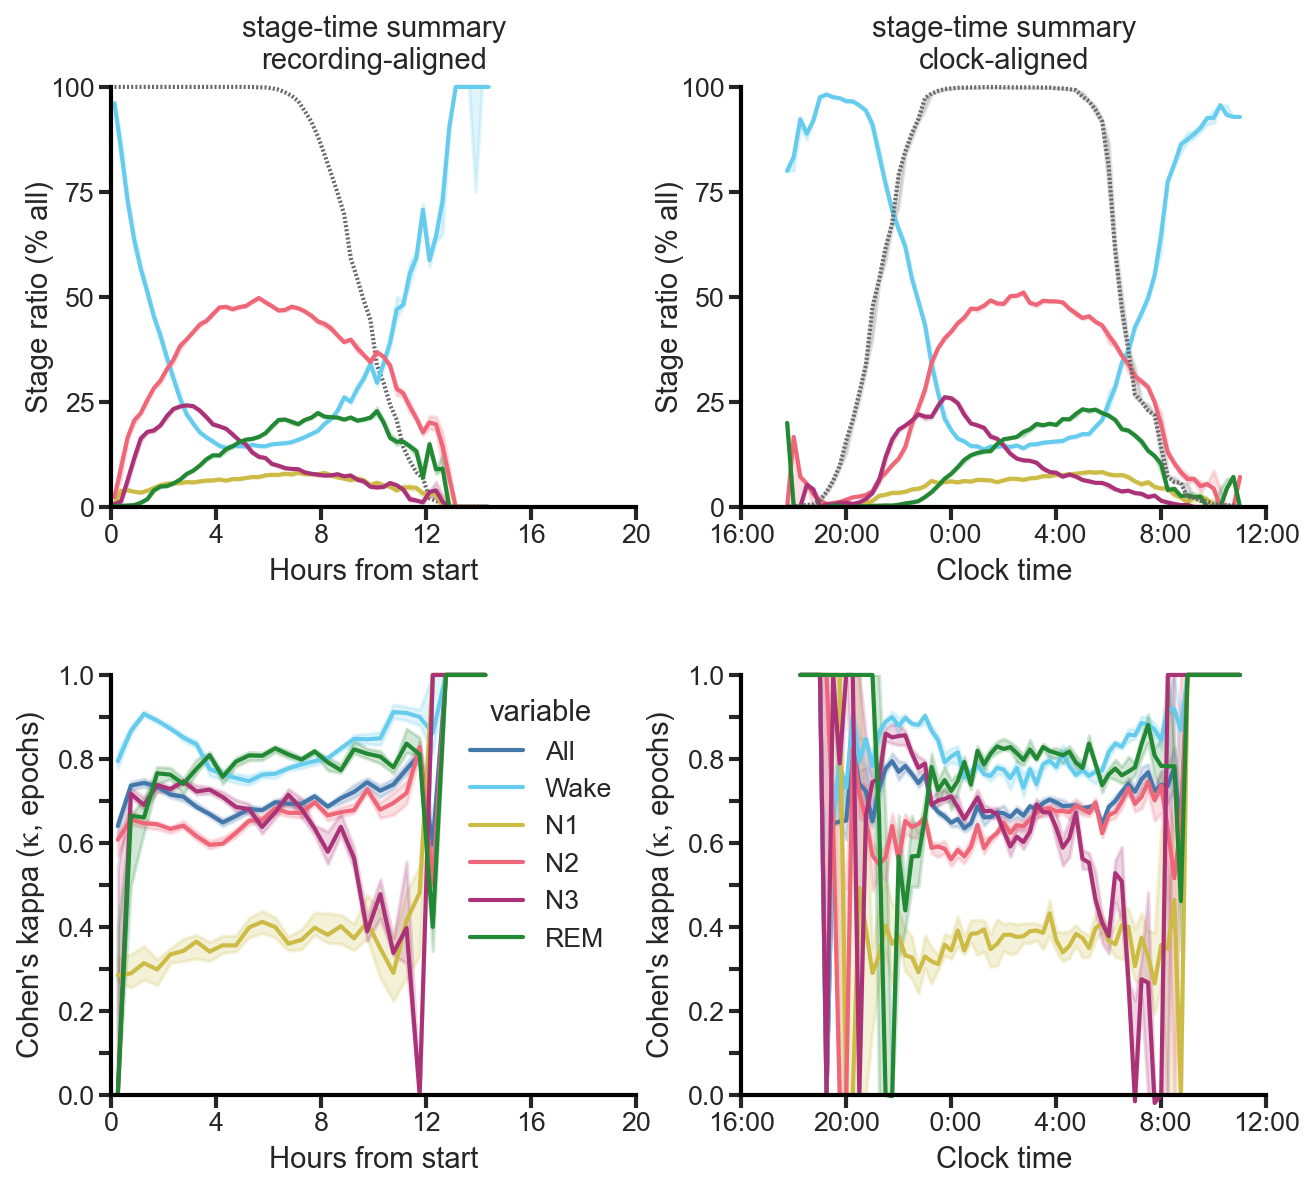

2015 SfN (k=0.280)

I gave my first talk at the 2015 Society for Neuroscience’s (SfN) annual meeting in Chicago. At the time, I was using combinations of “traditional” machine learning techniques on tons of hand-crafted features (from the RR itself, the spectrum of the RR, etc.), but the results were not great. The Cohen’s kappa was 0.28—pretty abysmal. I also presented a new parametric non-sinusoidal function that I found better matched the RR intervals during respiratory sinus arrhythmia (RSA) than a simple sine wave.

2017 SfN (k=0.530)

I presented these findings at the 2017 SfN meeting in D.C. on a “dynamic” poster (i.e., a large TV). The results were now a quite respectable Cohen’s kappa of 0.530—better than state-of-the-art on 5-stage scoring for “EEG-less” methods (any method for sleep staging that makes no use of brain, i.e., EEG data). For reference, the current state-of-the-art on 5-stage scoring was k=0.510 from Sady et al, 2013 [1].

2018 SfN (k=0.710)

I gave my second talk at the 2018 SfN meeting in San Diego, where I demonstrated that we had reached a Cohen’s kappa of 0.710 on 5-stage scoring. We were now significantly better than state-of-the-art, and finally within the range of expert human-scored PSG.

In 2020 a new, published, state-of-the-art threshold was reached for EEG-less methods, k=0.585 from Sun et al. [2]. However, unbeknownst to anyone that didn’t attend my 2018 SfN talk, this was significantly below the k=0.710 I had already presented.

2024 CIBM (k=0.725)

To address the biggest concern from the initial round of reviews, I taught myself about meta-analyses and non-inferiority testing. And, after another two rounds of reviews, the paper was accepted by CIBM on April 28th.